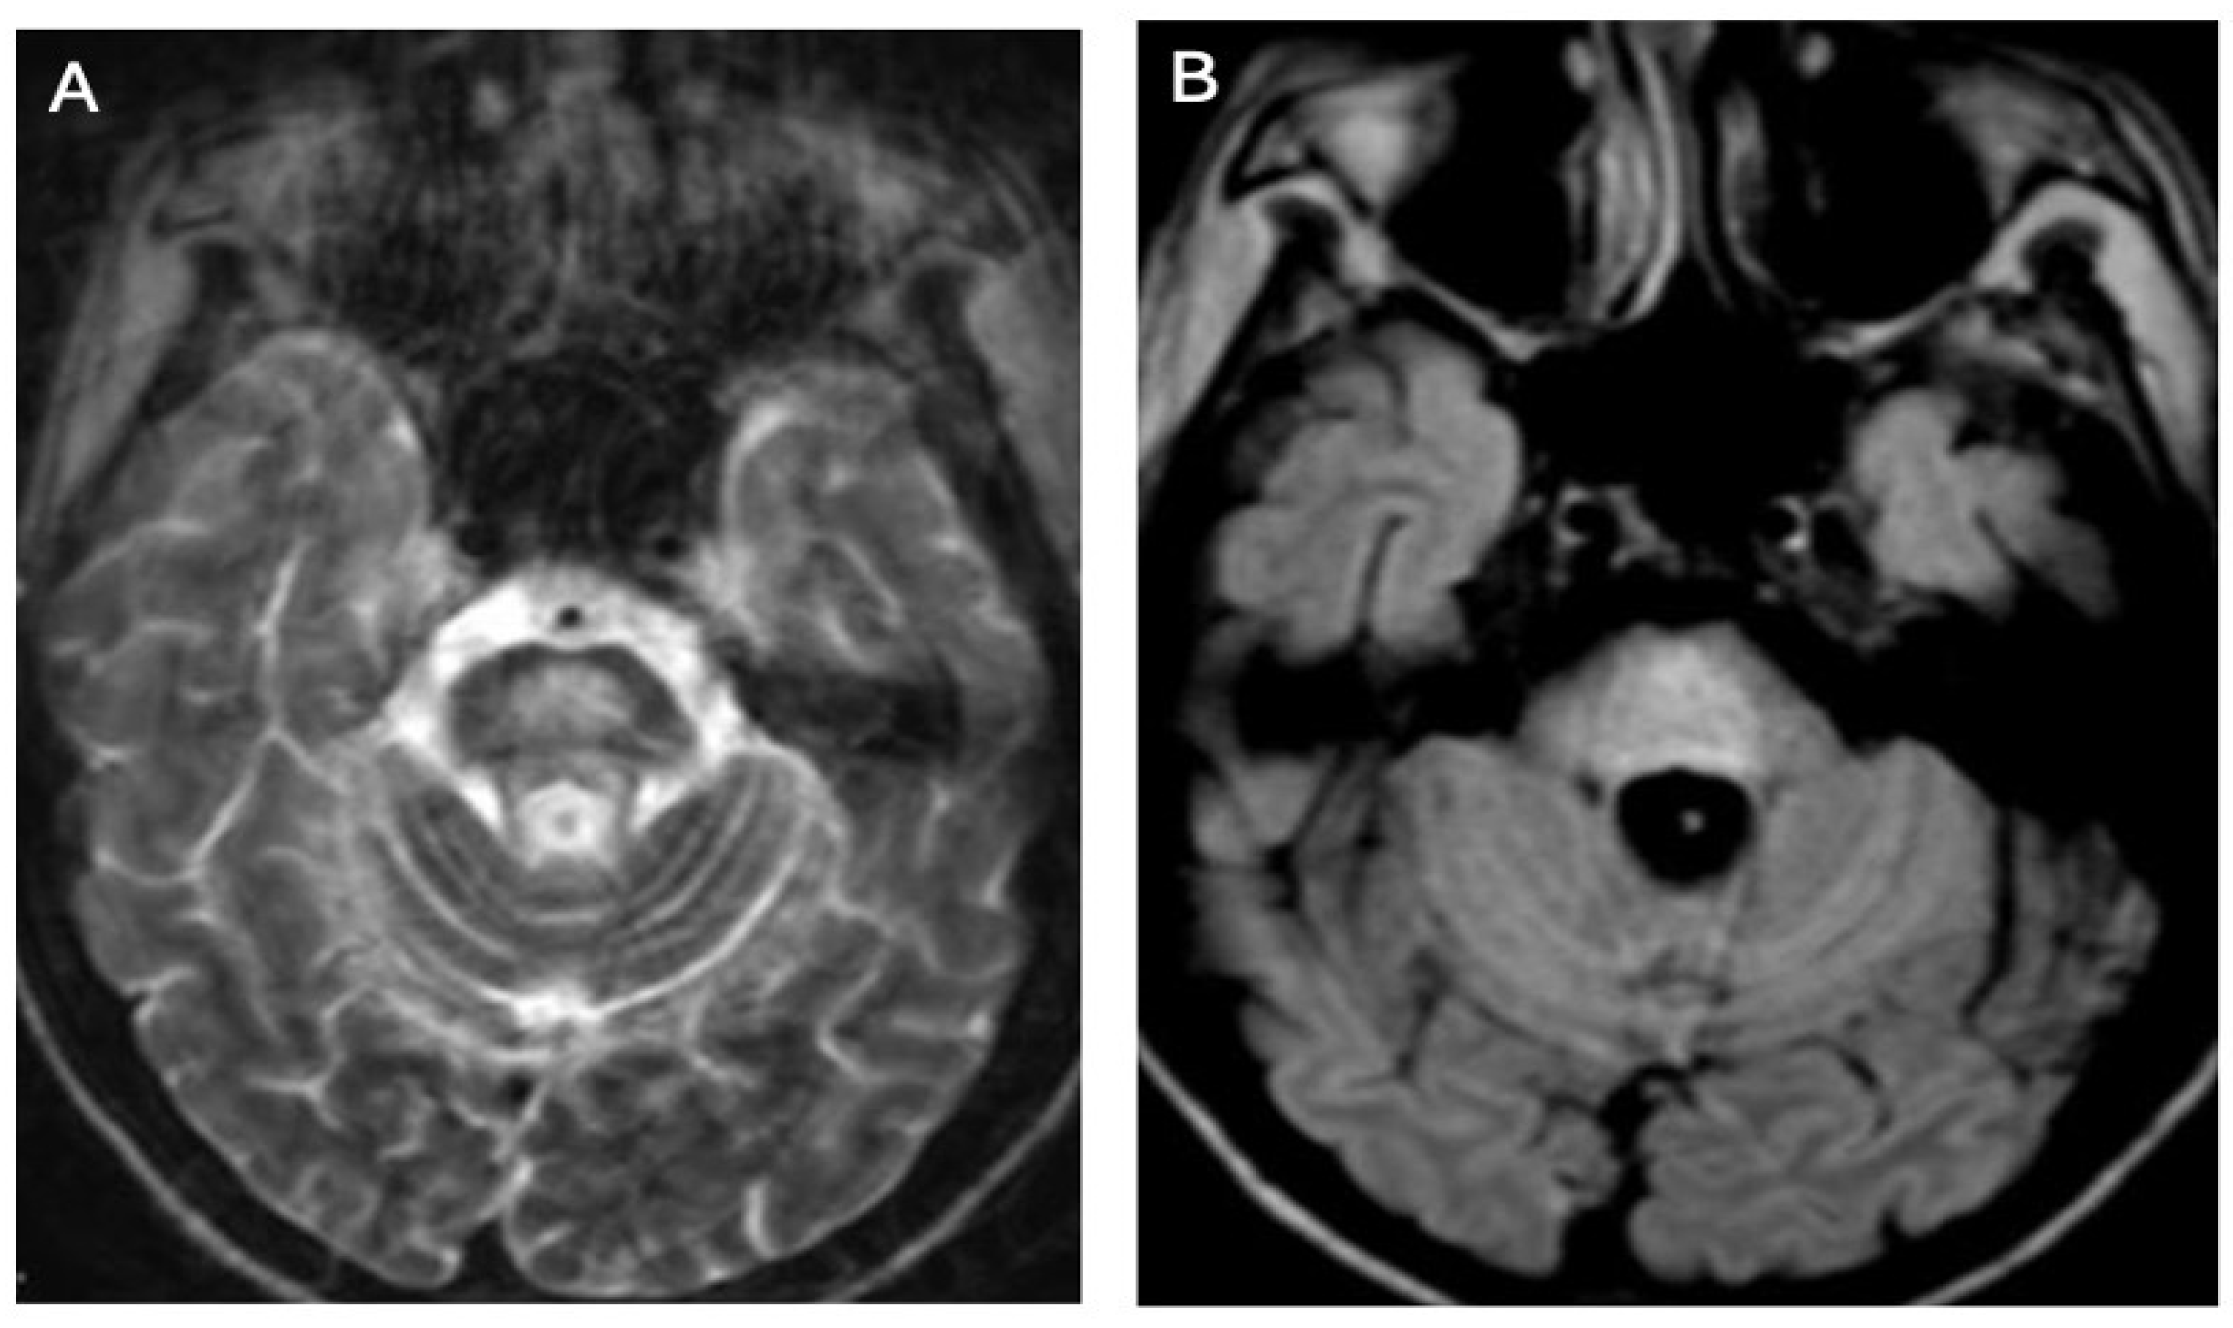

3.1. Classical Brain MRI Examination in WD Patients

3.2. Diffusion MRI in WD